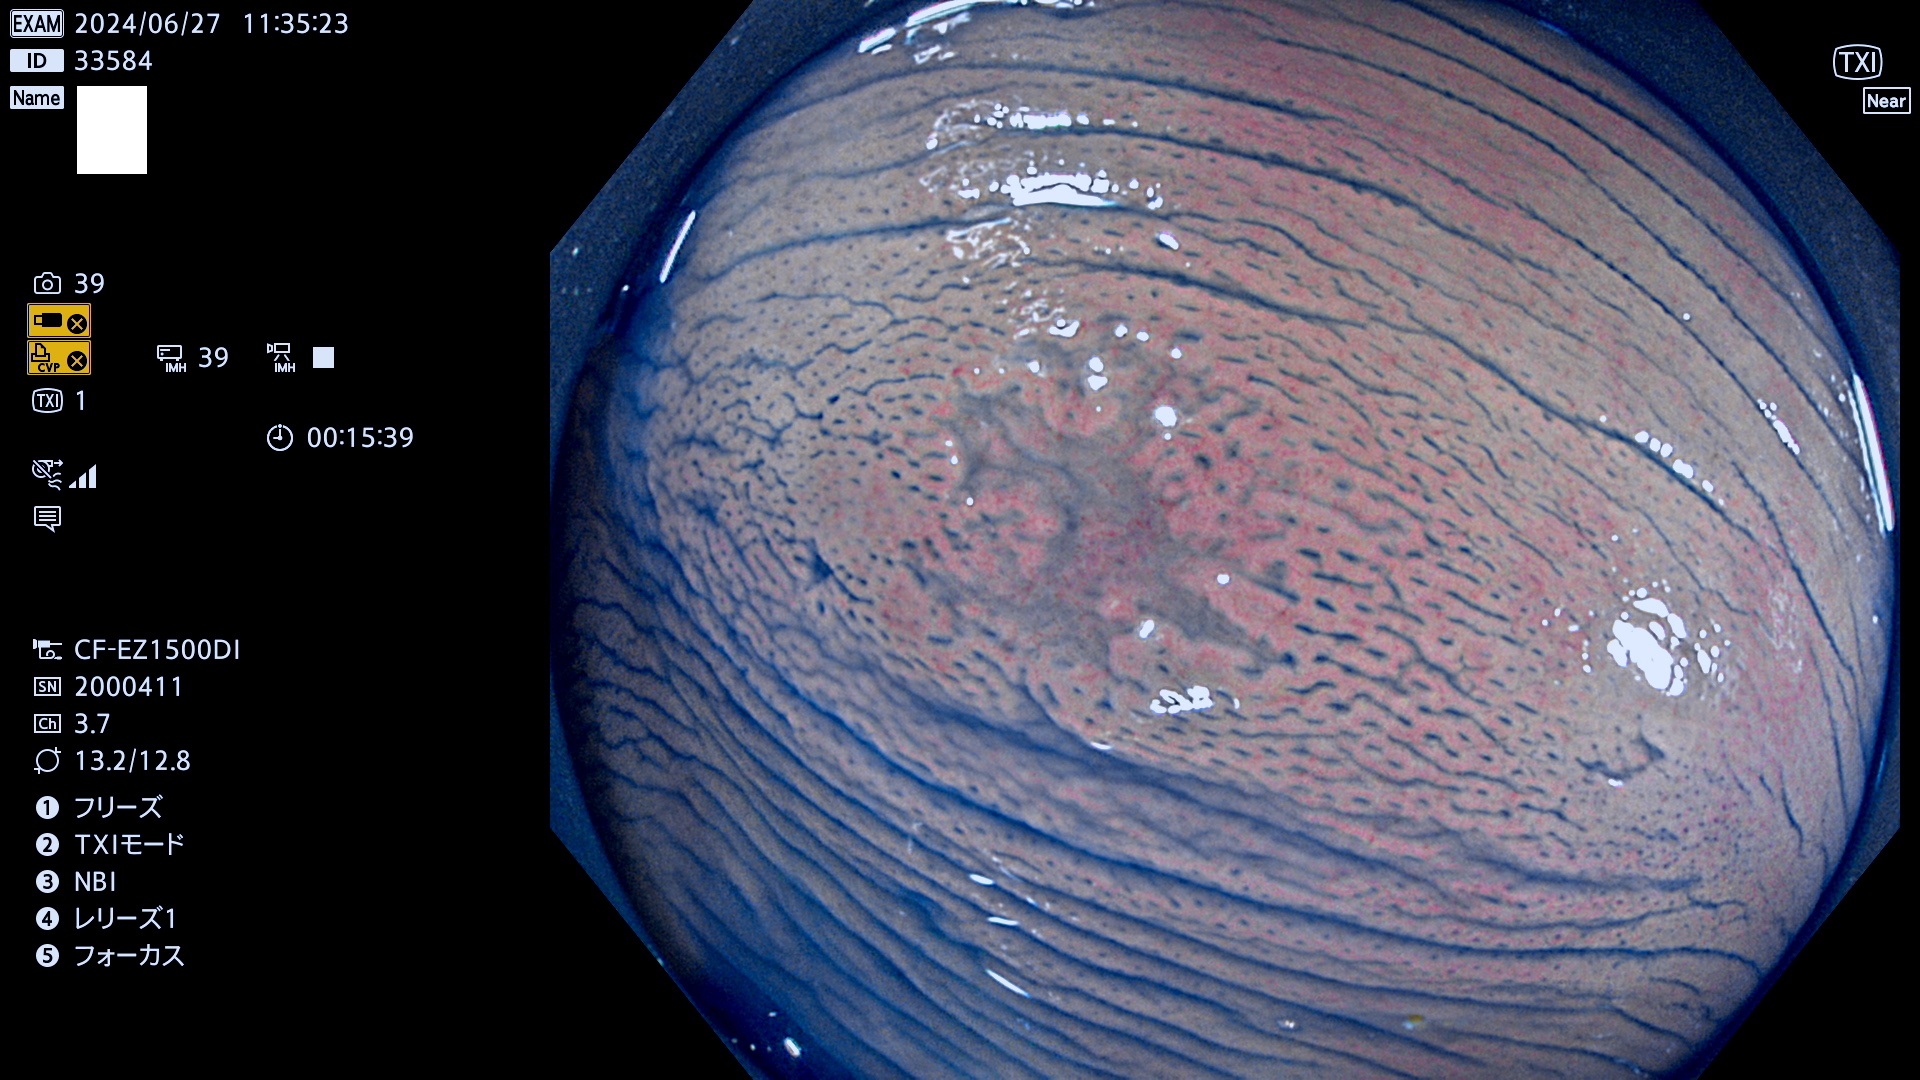

完全に平坦な物をUb、陥凹している物をUcと呼びます。最も発見が難しく危険な病変です。

抽出の対象期間 2024年6月27日〜7月1の5日間(40件の検査)6件 (6/40=15%)